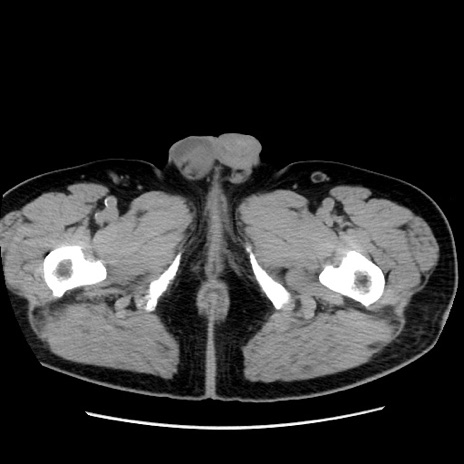

冠状断像